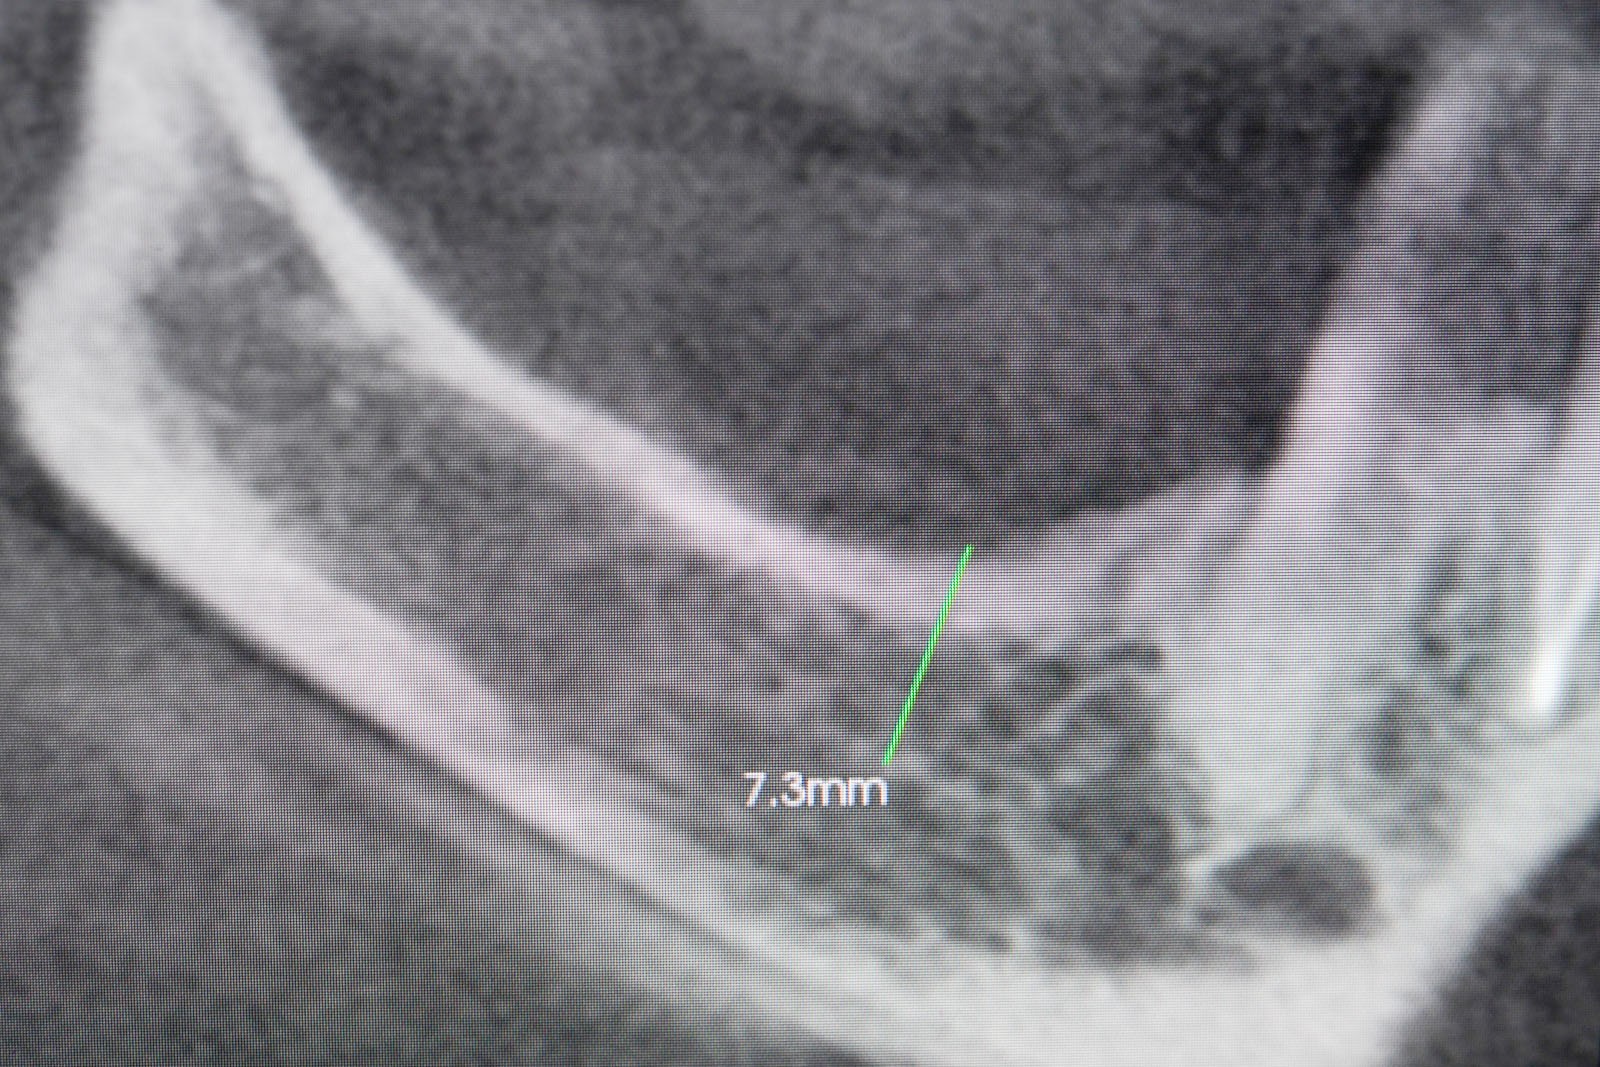

• Metoda otwarta – opisana w 1980 przez Jamesa i Boyna – polega na chirurgicznym dostępie do zatoki szczękowej poprzez jej boczną ścianę, następnie delikatnej preparacji, oddzieleniu wyściółki (błony Schneidera) bez jej perforacji, umieszczeniu pomiędzy nią a dnem zatoki materiału odbudowującego kość. Zabieg podniesienia dna zatoki szczękowej może przebiegać z jednoczesnym wszczepieniem implantów lub wszczepieniem ich w czasie odroczonym o 6–8 miesięcy. Warunkiem jednoczesnego wszczepienia implantów jest możliwość pierwotnie stabilnego ich umocowania w pozostałej własnej kości wyrostka zębodołowego. Najmniejsza jej ilość wg niektórych autorów to 1 mm.

• Metoda zamknięta – opisana w 1994 przez Summersa – bez szerokiego otwierania zatoki szczękowej, stosowana w sytuacjach wymagających niewielkiego zakresu rekonstrukcji na wysokość. W tej metodzie materiał regeneracyjny do odbudowy kości wprowadza się przez nawiercony kanał, komunikujący się z zatoką w pozycji zaplanowanej do wszczepienia implantu, lub tylko kondensuje się (zagęszcza, rozpycha i wydłuża) obszar kości dla uzyskania stosownej jej ilości i gęstości dla stabilnego umocowania implantu. Zabieg odbudowy kostnej wg Summersa wykonuje się przy użyciu specjalnego instrumentarium – zestawu osteotomów. Uzyskuje się dodatkowo 2–4 mm kości na wysokość